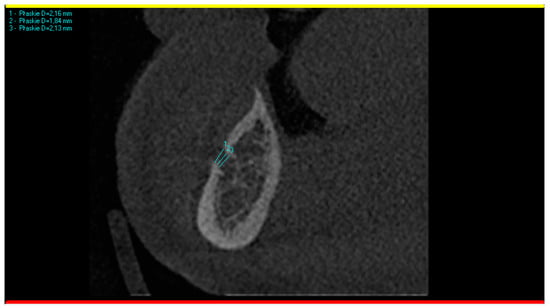

Fortunately, the patient felt relief just a few minutes after administration of the block anesthesia at the mental foramen. As the approximate cause was related to a mental nerve, the CBCT was analyzed again. Having in mind the hypothesis of professors Pawela and Wnukiewicz, the diameters of the metal foramina were analyzed in comparison with the inferior alveolar canal and with the opposite side. To obtain the most reliable result, each mental foramen was measured three times, and then, the mean vertical diameter was calculated. The measuring was conducted on a CBCT cross-section perpendicular to the panoramic curve, as presented in Figure 2.

Figure 2. CBCT scan showing the methodology of measuring the mental foramen. Three measurements were taken (results 2.16, 1.84, and 2.13 mm are visible in the upper left corner) and then the mean diameter was calculated (2.04 mm) to obtain the most reliable result.